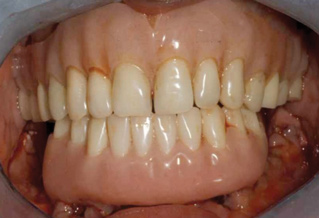

Fig 14. Final restorations used for 6-1/2 additional years.

Figure 14

This is an unfortunate mindset in that current advances in protocol and technology can result in significant advantages in addressing some or most of these concerns. The patient shown in Figure 12 may serve to illustrate this point. She had a destroyed maxillary dentition, a less-compromised but highly unesthetic mandibular component, and a single goal: to be able to "smile at my grandchildren again." In consultation with her and her family, it was decided that a double-arch fixed implant approach would most realistically address her esthetic goals and provide her with the desired prosthetic result. She was 102 years old at the time of initial consultation. Using a staged operating-room approach, provisional restorations were initially delivered, followed by subsequent definitive hybrid final restorations. She was able to use these comfortably for the next 6-½ years (Figure 13 and Figure 14).